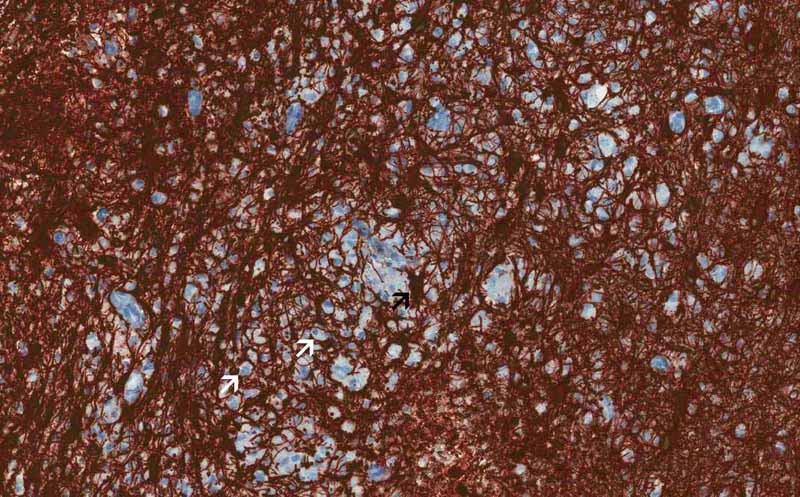

Immunohistochemistry

Glial fibrillary acidic protein (GFAP): GFAP is also an intermediate filament and is found in astrocytes. The image here demonstrate a dense mesh of GFAP cytoplasmic processes with foamy macrophages (white arrows) scattered in between. Astrocytes has star like processes which makes them look like a star and hence their name (black arrow). Click here to see another image of stellate shaped reactive astroytes stained for GFAP. This dense mesh of astrocytes is abnormal and is resulted from proliferation of reactive astrocytes due to the demyelinating process.